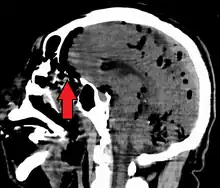

Large pneumocephaly secondary to surgical wound

CT scans of patients with a tension pneumocephalus typically show air that compresses the frontal lobes of the brain, which results in a tented appearance of the brain in the skull known as the Mount Fuji sign.[1][2][3] The name is derived from the resemblance of the brain to Mount Fuji in Japan, a volcano known for its symmetrical cone. In typical cases, there is a symmetrical depression near the midline (such as the crater of a volcano), due to intact bridging veins.[3] Its occurrence seems to be limited to tension pneumocephalus (not occurring in pneumocephalus without tension).[4] The sign was first described by a team of Japanese neurosurgeons.[5]